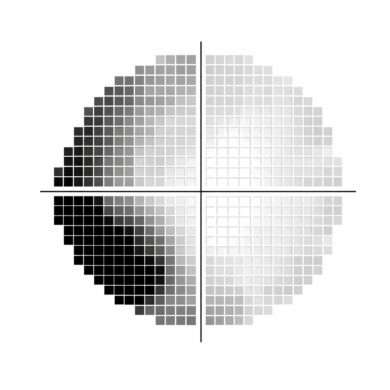

グレースケールとは、感度の数値(dB)を濃淡で視覚的に表示した図です。

「実測閾値」「TD」「PD」それぞれに対応したグレースケールが存在します。

- 実測閾値:今回の検査で得られた生データ

- TD:同年代の健常者との比較結果

- PD:全体的な感度低下を補正し、局所異常を強調した結果

ハンフリー視野計の検査結果では、上部に表示されているのがこのグレースケールです。左が実測閾値、右がそのグレースケールです(画像準備中)。